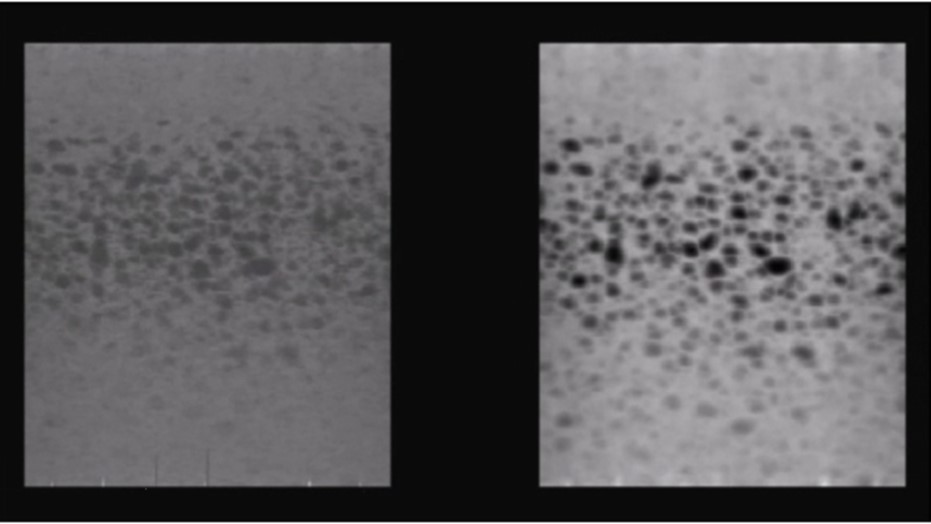

Probes with high acoustic contrast (32.63 dB to 36.66 dB) generated high quality images, Figure 3. Those with acoustic contrast values from 20 dB to 25 dB produced images of lower quality, Figure 4. A typical image produced by a damaged transducer measured as having an acoustic contrast of only 14.68 dB is shown below, Figure 5.

Figure 5.Random Void Phantom) - damaged transducer with inadequate contrast resolution (14.68 dB, Alloca SSD P52105). Original 3D rendered image (left), with increased image contrast (right). Small voids within the RVP with weak contrast cannot be visualised.